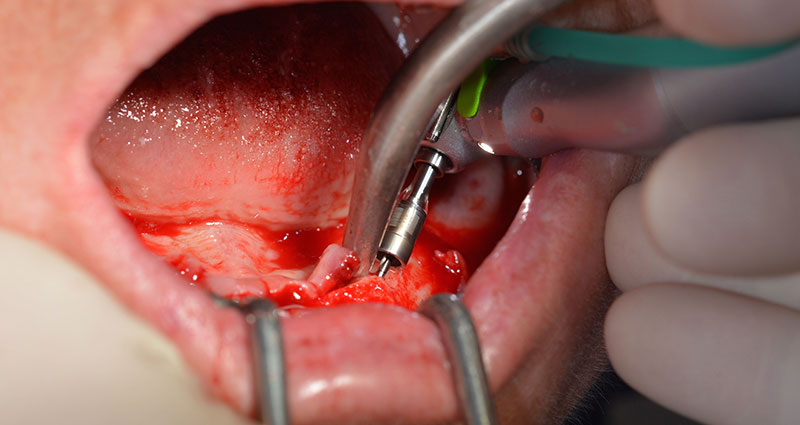

The surgical protocol for the implants employed (SKY, bredent medical) specifies a speed of 1,200 rpm for the pilot drilling (Fig. 7 - 9).

This corresponds to the next preset position in the Implantmed. Here we see the W&H contra-angle handpiece being held at a 45° angle to mesiocaudal in the region of 45 in order to preserve the mental nerve. The mental foramen is used as the anatomic reference for all drilling in this region. The subsequent holes were drilled at a reduced speed of 300 rpm (Fig. 10 and 11).